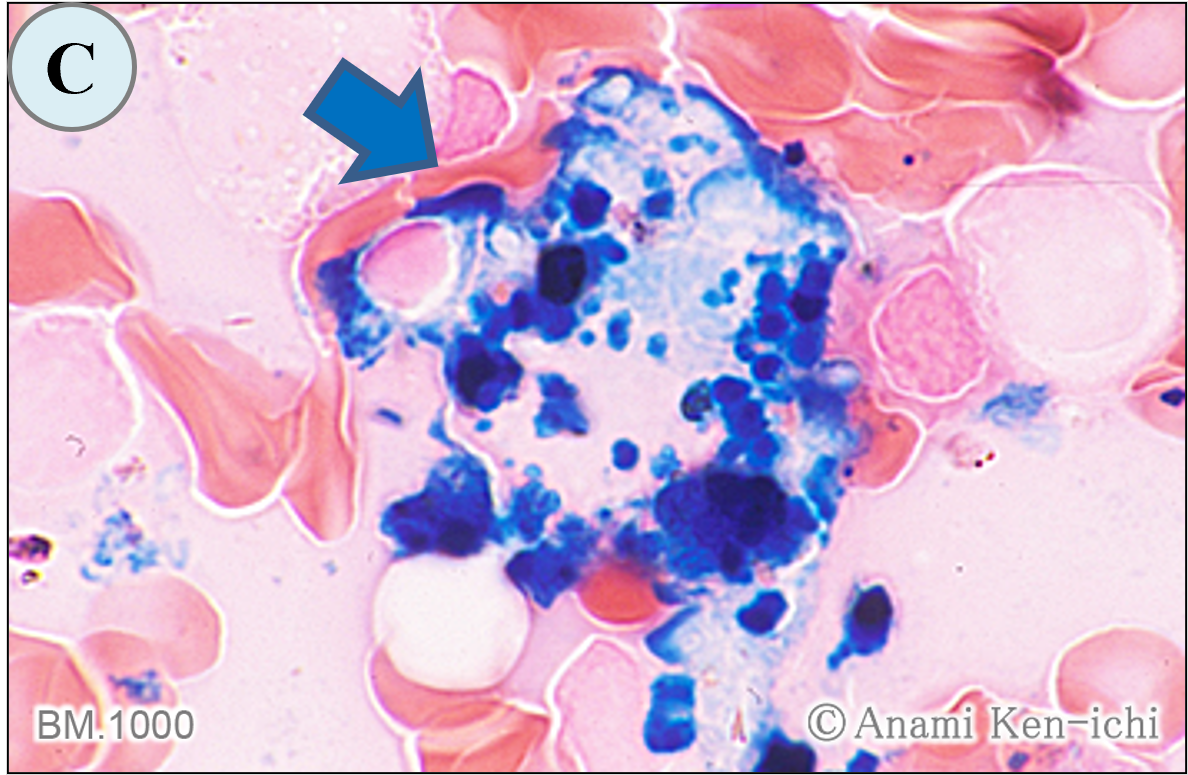

染色の種類と細胞の判別をお答えください。

BM.1000

D. アセテート・エステラーゼ染色です。本例は、AML-M5の分化型の症例で、単球系の腫瘍細胞(矢印)がびまん性陽性を呈したものです。本染色は非特的エステラーゼ染色の1つですが、陽性所見がびまん性に染まるために弱陽性の判定には困難なことが多く細心の注意を払う必要があります。